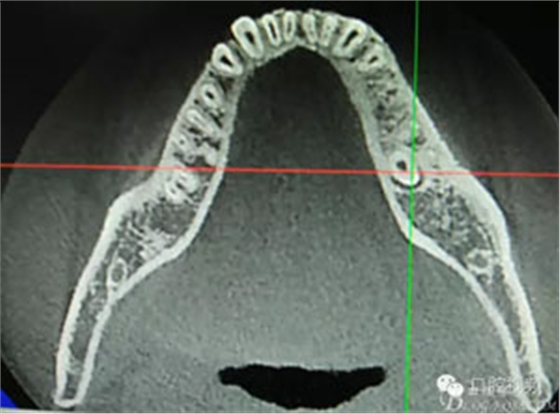

患者、盧xx、男、19歲。主訴:左側(cè)下頜乳磨牙未脫落,要求檢查。??茩z查:左側(cè)下頜第二乳磨牙有充填物。無(wú)松動(dòng),全景片檢查。35移位至36、37之間。頰舌側(cè)均不能觸及隆起。CBCT檢查:35位于36、37的舌側(cè)。表面骨質(zhì)約2mm左右。35完全骨埋伏,36的遠(yuǎn)中牙根疑是吸收。建議35暫觀察。置留不取?;颊咭蟀纬龘?dān)心壓迫36牙根或者發(fā)生囊性變。術(shù)前簽手術(shù)同意書。

圖2.術(shù)前的CBCT,35移位至36、37之間的舌側(cè)。